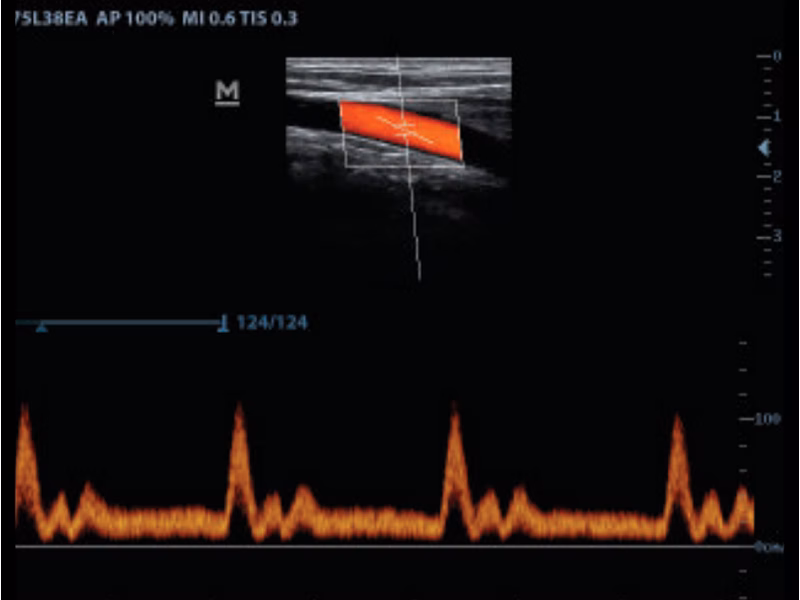

“Power Doppler ve Pulse Wave yazılımları vasküler yapıları tanımlar ve akımların hız grafiklerini elde ederek Dp50 Vet’i siyah beyaz ultrason sisteminin ötesine taşır!”

Power Doppler & Pulse Wave